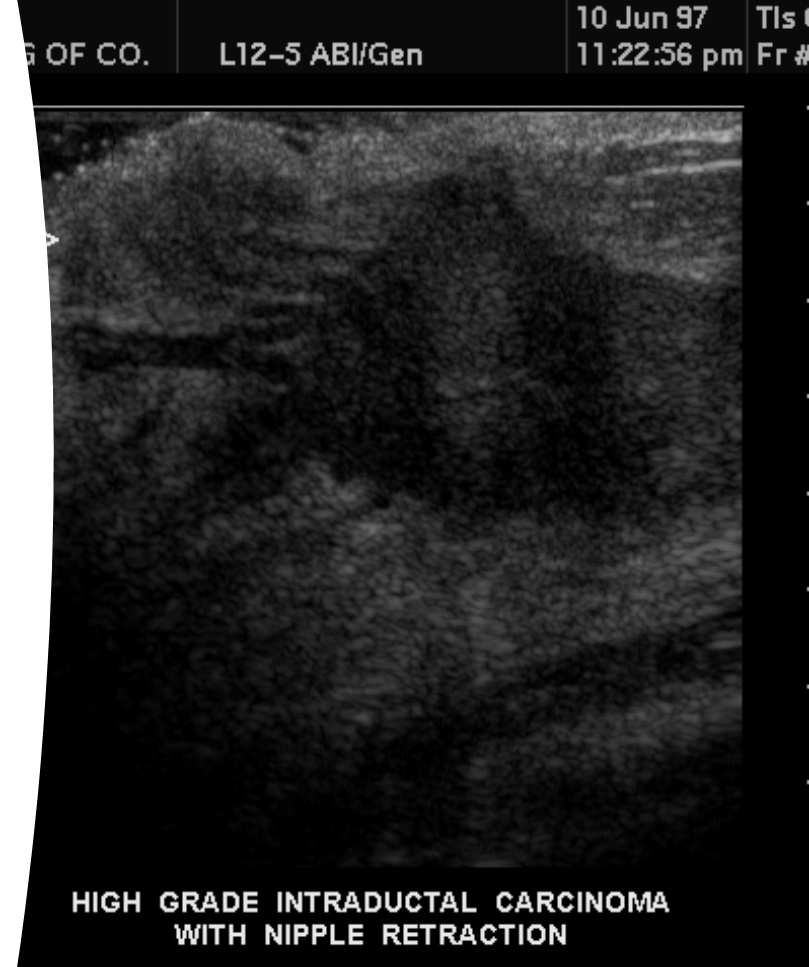

What is this image showing?

intraductal carcinoma